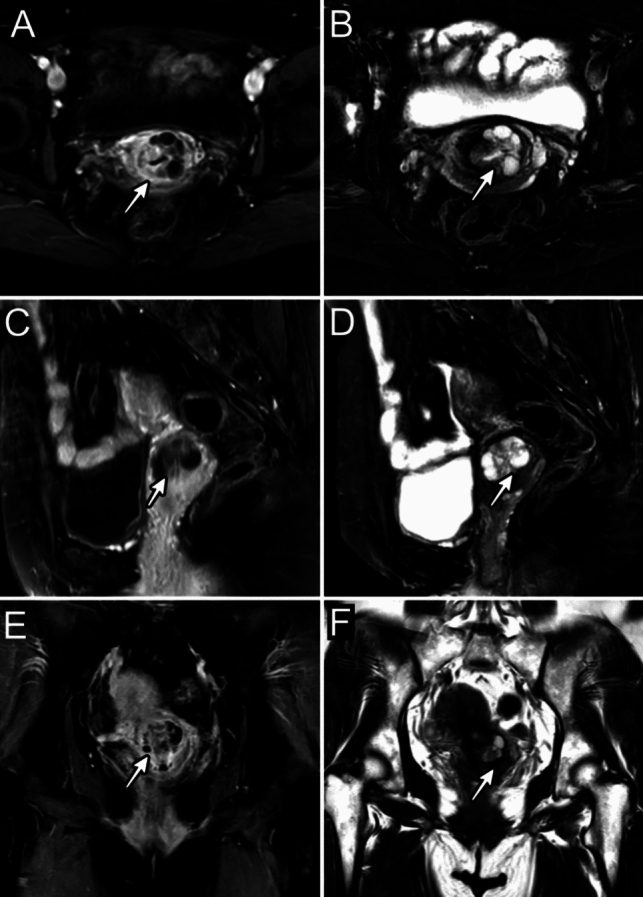

We present the first documented case of gastric-type endocervical adenocarcinoma in situ in a mosaic STK11 pathogenic variant carrier, who delivered a child with classic Peutz-Jeghers syndrome (PJS). A 53-year-old woman presented with persistent watery vaginal discharge for 2 years. Histopathology confirmed gastric-type endocervical adenocarcinoma in situ. Familial genetic investigation was initiated after her son's diagnosis of PJS with an apparent de novo STK11 germline variant [NM_000455.4:c.842del (p.Pro281Argfs*6)]. Comprehensive STK11 screening via Sanger sequencing of peripheral blood from both parents showed no pathogenic variants. Following multidisciplinary tumor board review, ultra-deep next-generation sequencing was performed on multiple tissue specimens. Molecular analysis revealed low-level mosaicism for the familial STK11 variant in cervical tissue with no detectable mutations in blood, saliva, urine, or ovarian stroma. This case demonstrates three key clinical insights: (1) parental mosaicism may underlie apparent de novo PJS cases, (2) tissue-specific STK11 mosaicism can manifest as localized neoplastic transformation without classic PJS manifestations, and (3) ultra-deep sequencing may be considered in genetic counseling paradigms for parents of children with "de novo" cancer predisposition syndromes. These findings highlight the importance of considering mosaic phenomena in tumor prevention for hereditary cancer syndrome families.